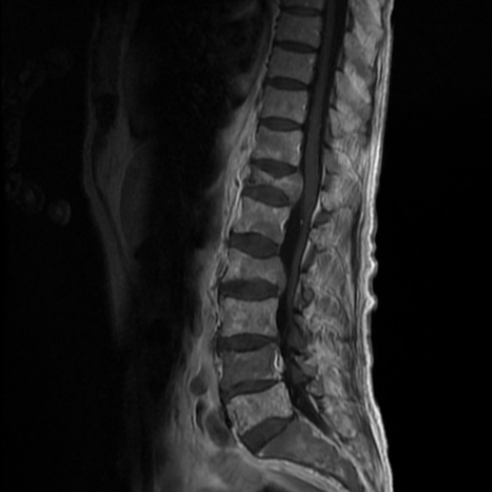

Imagine RMN al unui pacient cu fracturi tasare pe fondul unor metastaze vertebrale ale unui melanom malign

De asemenea medicul vă poate indica un examen de Rezonanţă Magnetică Nucleară (RMN), care facilitează diagnosticul şi oferă informaţii despre vechimea fracturii, despre măduva spinării, elementele nervoase şi discurile intervertebrale.